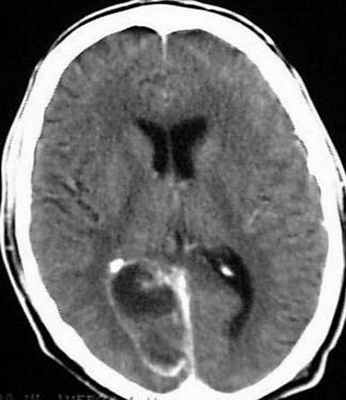

Начальная стадия соответствует ограниченному энцефалиту (церебриту) и обычно характеризуется не резко выраженными изменениями неспецифического характера на фоне обострения хронического гнойного среднего отита – нелокализованной головной болью, недомоганием. Впоследствии происходит ограничение (барьеризация) воспалительного процесса, сопровождаемое минимизацией клинических проявлений заболевания (латентная стадия). Для этого периода характерно отсутствие какой-либо отчетливой симптоматики. Важными клиническими признаками сформированного абсцесса мозга (явная стадия) являются общеинфекционые (слабость, повышение температуры тела, изменения в периферической крови), общемозговые (головная боль, тошнота, рвота, брадикардия, застойные изменения на глазном дне) и очаговые симптомы. Последние зависят от локализации абсцесса. К признакам абсцесса височной доли относят контрлатеральный гемипарез, центральный паралич лицевого нерва, судороги, атаксию, нарушения вкуса и обоняния, гомонимную гемианопсию, алексию, аграфию, а при поражении доминантной доли – сенсорную и амнестическую афазию. К очаговым симптомам абсцесса мозжечка относят координационные расстройства, понижение сухожильных рефлексов на стороне поражения, появление патологических рефлексов и др. При вторичном гнойном менингите у больных с абсцессом мозга наблюдается менингеальный синдром с характерными изменениями спинномозговой жидкости. Вместе с тем многообразие клинических проявлений отогенного абсцесса мозга, его частое сочетание с другими внутричерепными осложнениями затрудняют своевременную диагностику. Именно поэтому одним из наиболее эффективных методов диагностики отогенных абсцессов мозга является КТ [24–26]. При проведении КТ визуализируется участок мозга пониженной плотности с ровными краями и выраженной зоной перифокального отека, усилением визуализации капсулы при введении контрастного вещества [27].

Для того чтобы провести точную диагностику места расположения абсцесса мозга и мозжечка, проводят компьютерную и магнитно-резонансную томографию головного мозга. При проведении компьютерной томографии выявляется тонкая, гладкая стенка абсцесса, которая имеет правильные контуры. Магнитно-резонансная томография позволяет также определить капсулу абсцесса. Если нет возможности провести вышеперечисленные виды исследования, можно провести пневмоэнцефалографию или радиоизотопную сцинтиграфию головного мозга.